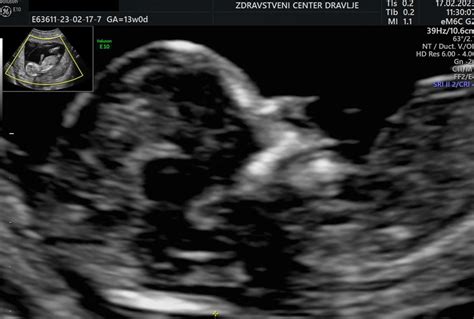

Pregled nuhalne svetline je ključni ultrazvočni test, ki se izvaja v zgodnji nosečnosti, natančneje med 11. in 13. tednom. V tem obdobju je plod dolg med 45 mm (11. teden) in 84 mm (13. teden), kar omogoča natančno merjenje. Bistvo preiskave je merjenje debeline tekočine na hrbtni strani otrokovega vratu, imenovane nuhalna svetlina. Ta meritev je pomembna, ker lahko povečana debelina nuhalne svetline nakazuje na večje tveganje za določene kromosomske nepravilnosti, kot so Downov sindrom (trisomija 21), Edwardsov sindrom (trisomija 18) ali Patauov sindrom (trisomija 13), pa tudi druge strukturne ali srčne napake.

Poleg meritve nuhalne svetline, med pregledom ginekolog podrobno preveri še druge pomembne parametre razvoja ploda. To vključuje merjenje srčne frekvence, velikosti ploda od vrha glavice do trtice (razdalja teme-trtica), premer glavice, oceno prisotnosti in oblike nosne kosti (ki je pri plodovih z Downovim sindromom pogosto odsotna ali prekratka), preverjanje oblike glavice in možganskih struktur, pregled srca, želodčka in mehurja ter preverjanje celovitosti trebušne stene. Ocenijo se tudi dolge kosti na zgornjih in spodnjih udih ter hrbtenica. Dodatno se preveri lega posteljice in količina plodovnice. V tem zgodnjem obdobju je mogoče opraviti tudi zgodnjo morfologijo ploda, ki omogoča oceno anatomije otroka. V nekaterih primerih, čeprav še nezanesljivo, je mogoče že določiti spol otroka, saj se spolna diferenciacija zaključuje okoli 15. tedna.

Ultrazvočno merjenje nuhalne svetline je najprimerneje opraviti med 11. in 13. tednom nosečnosti, natančneje do dopolnjenih 13 tednov in 6 dni, ko je plod dolg do 85 mm. Po tem obdobju test še vedno lahko opravimo, vendar je manj natančen, saj se nuhalna svetlina začne zmanjševati in postaja težje merljiva. Ta časovni okvir je izbran tudi zato, ker omogoča pravočasno ukrepanje v primeru ugotovljenega visokega tveganja in potrebe po nadaljnjih diagnostičnih postopkih, vključno z možnostjo prekinitve nosečnosti, če bi se potrdile hude nepravilnosti.

Pred pregledom je pomembno, da ima nosečnica izpraznjen sečni mehur, kar omogoča boljšo vidljivost med transabdominalnim ultrazvokom (preko trebušne stene). V primeru slabe vidljivosti se lahko pregled opravi vaginalno. Za natančnost meritev je ključnega pomena tudi pravilna lega ploda.